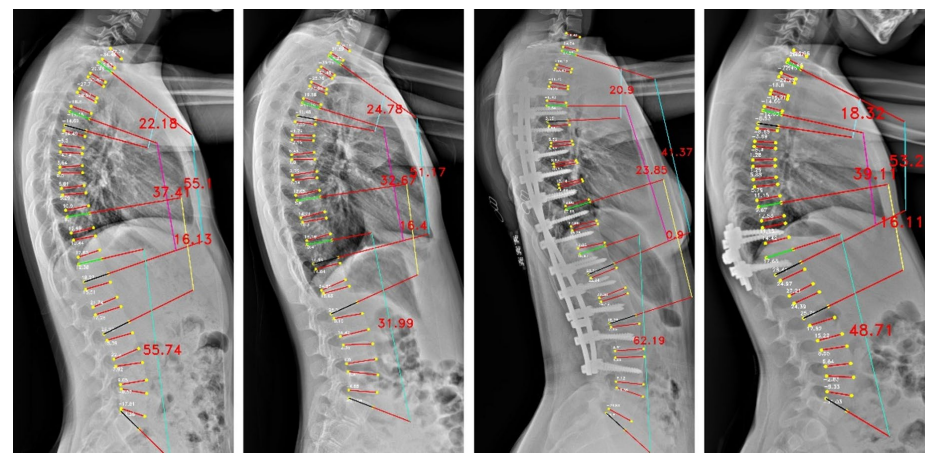

Cobb角是评估脊柱侧弯程度的"金标准",其测量结果可以用于评估病情、制定治疗计划和跟踪疾病进展。万东Cobb角自动测量系统,1秒内即可完成Cobb角计算,较传统手工测量(耗时>2 分钟)效率提升百倍。经研究验证,Cobb角平均测量误差仅3.918°,ICC为0.943,验证了该算法技术指标顶尖、误差小、重复性极好,相关论文收录于脊柱外科和脊柱研究领域的国际顶级期刊之一《European Spine Journal》。

The vertebrae four corner points and the Cobb angles measurement for LAT view images

基于负重位CBCT的全脊柱三维Cobb角自动测量,实现了椎体的高精度自动分割,其Dice系数达0.9776(自动分割的结果越准确,Dice值就越接近1),误差极小;三维Cobb角测量可接受度>97.05%,关键椎体识别准确率98.53%,显著优于传统方法。基于负重位CBCT椎体轴向旋转角度自动测量,与人工测量一致性ICC 达0.76,误差控制在±3.04° 内,实现了对椎体旋转的客观、高效、可重复测量,一键自动生成,高效助力临床精准诊疗。该研究入选中华医学会放射学学术大会(CCR 2025)。